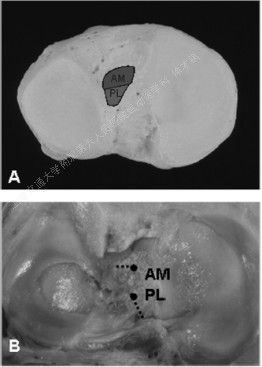

胫骨止点

→ACL胫骨止点——形态:卵圆形(Oval Shape)、C型(C Shape)。

→ACL股骨止点——分束:

Siebold认为:ACL并无AM、PL明显分束,仅为纤维束;止点均位于胫骨内侧髁间棘内侧,无PL束,而是PM束。

AM束:距胫骨前缘13-17mm,外侧半月板前脚边缘;

PL束:距胫骨前缘20-25mm,靠近外侧半月板后脚。